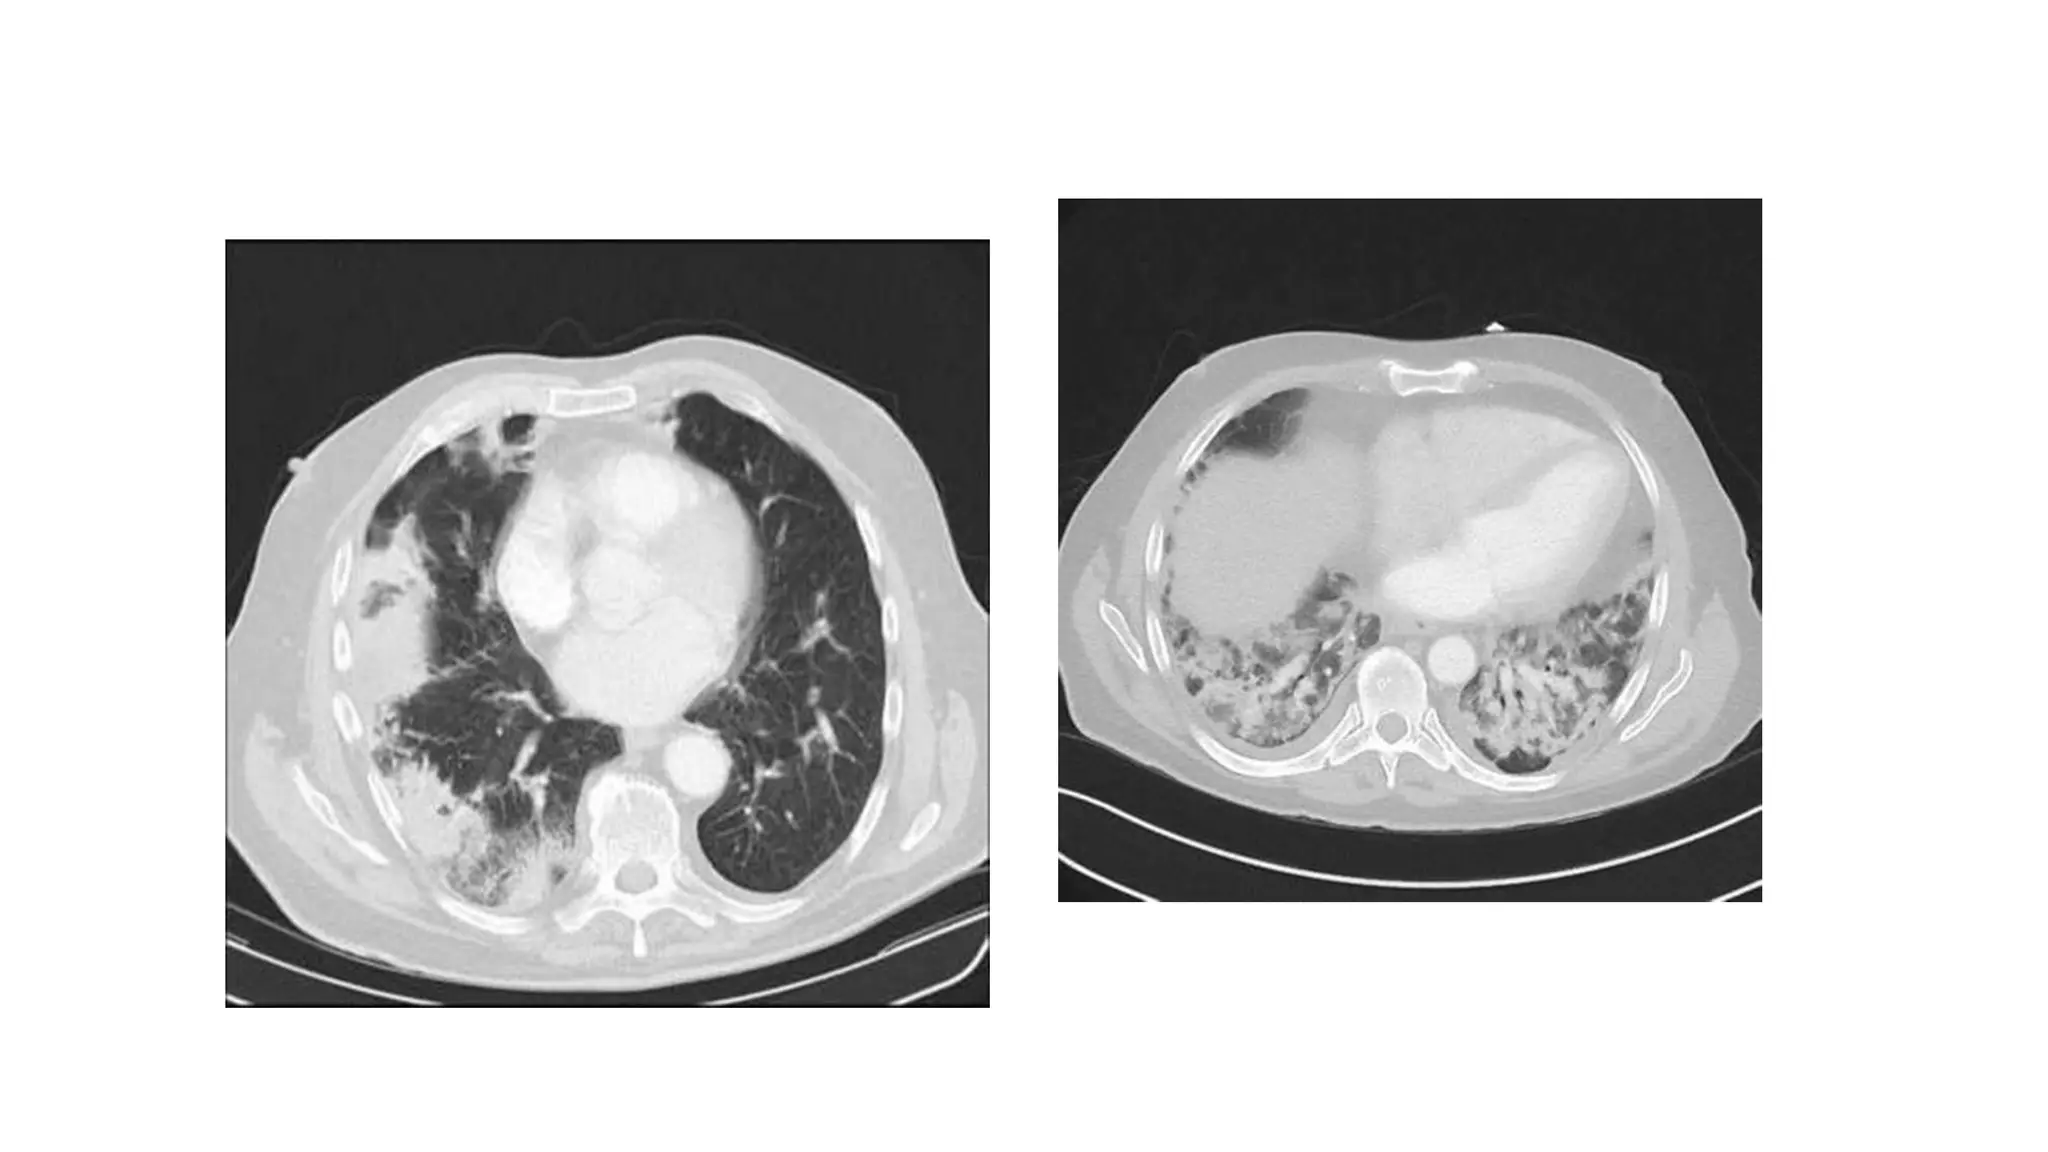

From cancerworld.net

Interstitial Lung Disease (ILD) as adverse event Cancerworld Magazine Ild Radiology Findings Interstitial lung disease (ild) is a term used to describe a heterogeneous group of lung disorders with characteristic. Until today, computed tomography (ct) is the most important and valuable radiological modality to detect, analyze, and diagnose diffuse. Interstitial lung abnormalities (ilas) are incidental computed tomography (ct) findings that are potentially compatible with interstitial lung disease (ild) in patients. This guide. Ild Radiology Findings.